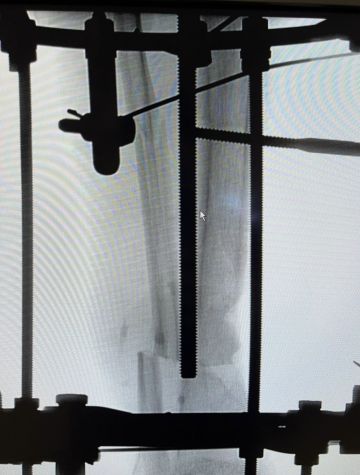

نجح فريق طبي في قسم جراحة العظام بمستشفى الإيمان العام، عضو تجمع الرياض الصحي الأول، في إجراء أول عملية تثبيت كسر مفتوح في عظم الساق اليمنى مع إطالة العظم لتعويض الجزء المفقود باستخدام تقنية “إليزاروف”، لمريض كان يعاني من كسر شديد التفتت وفقدان جزء من العظم منذ أكثر من ثلاثة أشهر إثر تعرضه لحادث مروري.

وأوضح استشاري جراحة العظام وقائد الفريق الطبي د. محمد عزمي أن المريض خضع للفحوصات الروتينية والأشعة السينية والمقطعية قبل إجراء العملية، والتي أظهرت وجود كسر مفتوح شديد التفتت مع فقدان جزء من العظم. وأضاف:

“تم تنفيذ العملية بتثبيت الكسر وإطالة الساق لتعويض النقص في الطول، وقد تكللت العملية بالنجاح ولله الحمد.”